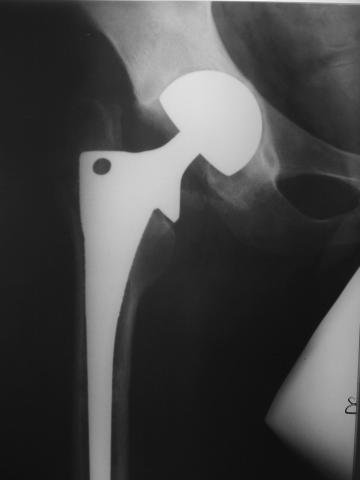

Уважаемые коллеги!молодой человек 22 лет обратился к нам с жалобами на умеренную боль в в/3 левого бедра и паху при ходьбе, укорочение левой ноги. 3 года назад получил закрытый перелом шейки левого бедра (рис 1).

Лечился в стержневом аппарате по месту жительства. АВФ демонтировали через полгода из-за воспаления в области стержней (рис 2). После демонтажа в течение месяца больной лихорадил до 38*, были боли в бедре. Эти явления исчезли после курса антибиотиков. Через год после травмы в ЦРБ ему имплантировали биполярный протез (рис 3). Рана зажила первично. Ходил с костылями, слегка приступая на ногу. На контрольных осмотрах выявлена прогрессирующая протрузия (рис 4-6).